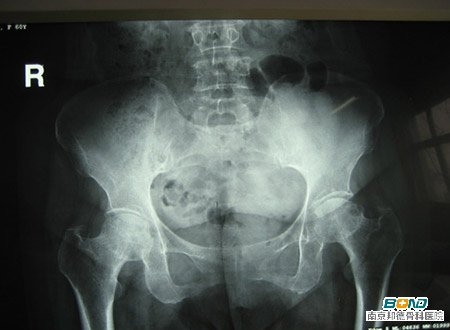

髋关节炎的症状有哪些?

髋关节炎是指由于髋关节面负重不均衡所致的关节软骨变性或骨质结构改变的一类骨关节炎性疾病。其主要表现为臀外侧、腹股沟等部位的疼痛(可放射至膝)、肿胀、关节积液、软骨磨损、骨刺增生、关节变形、髋的内旋和伸直活动受限、不能行走甚至卧床不起等。